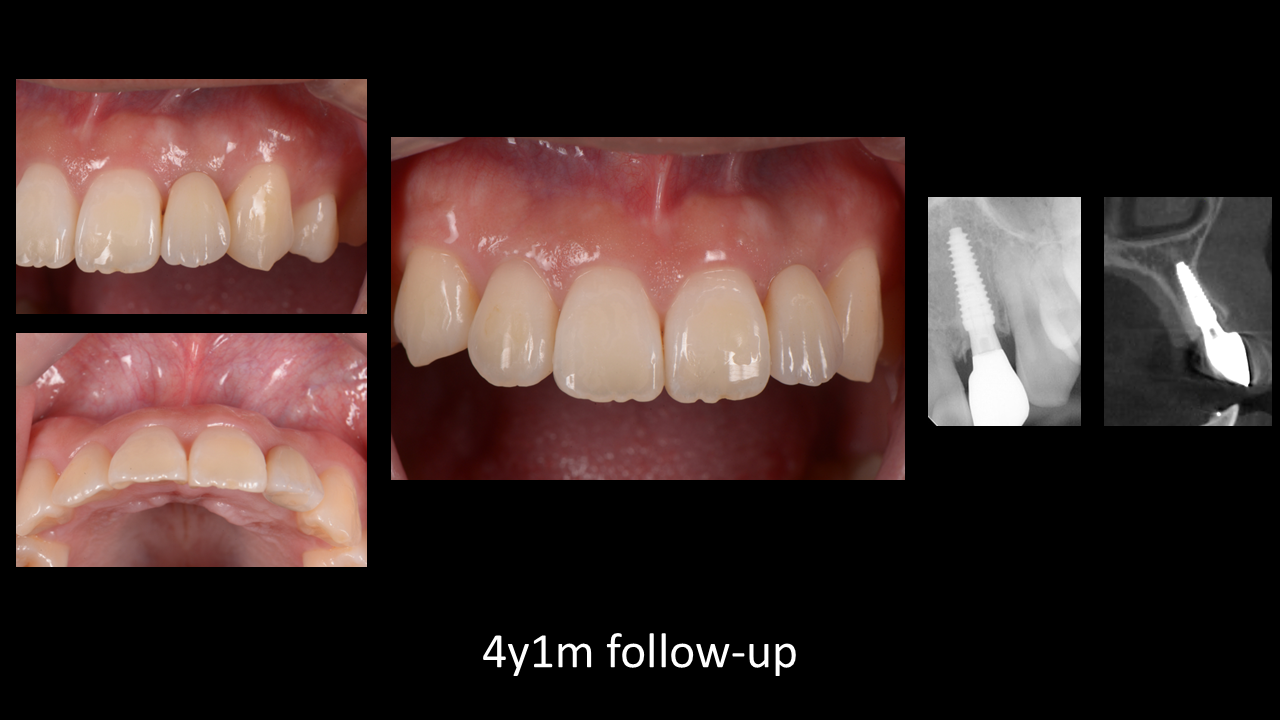

8787.png4年経過時の写真はこちら!安定しています